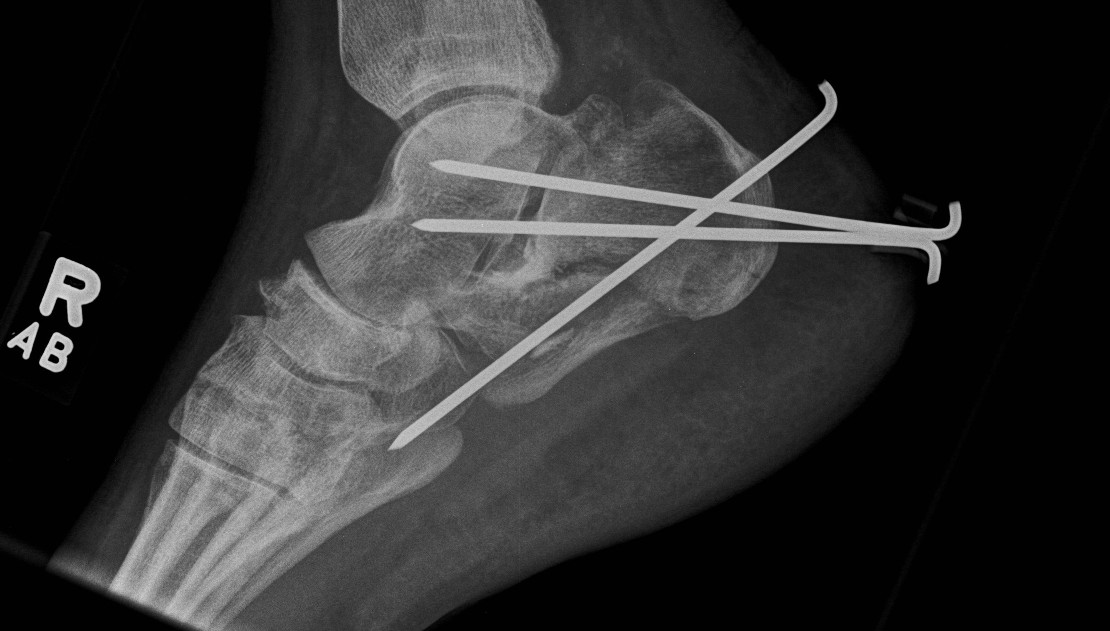

- 287 displaced intra-articular fractures

- MUA / Gissane spike percutanous reduction / K wire fixation

- 72% good or excellent results

- 1.7% deep infection, 7% superficial infection

Percutaneous Fixation